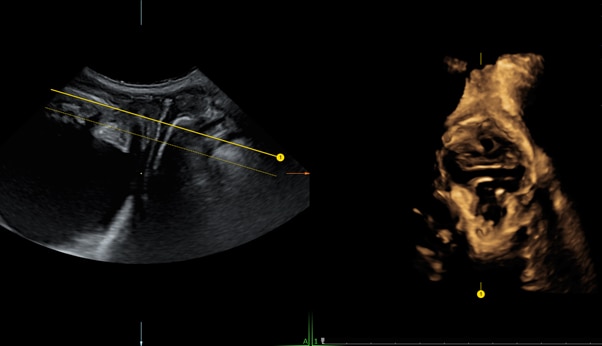

The use of ultrasound as a diagnostic tool in: Pelvic Floor.- How to optimize 2D image quality before collecting your volume.